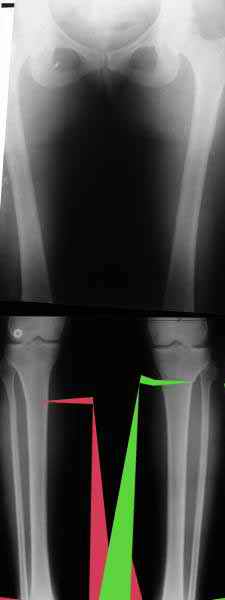

Вот, с учетом и без учета, и на разных уровнях...